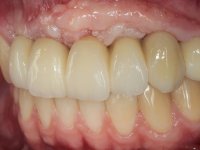

10 weeks after the surgery, a first impression was done to do a CAD-CAM provisional bridge (based on the diagnostic wax-up), that worked the soft tissue architecture during two months. This architecture was copied in a second impression by individualizing the impression copings in their emerging profile.

The working model was scanned and the dental technician developed a zirconia framework based on the diagnostic wax-up. This framework try-in was done, the perfect fit was assessed, and a final impression was done with a light silicone.

The bridge was finally placed with a progressive screwing to allow the tissue to accommodate the pressure of the pontics and the abutments emergency profiles.